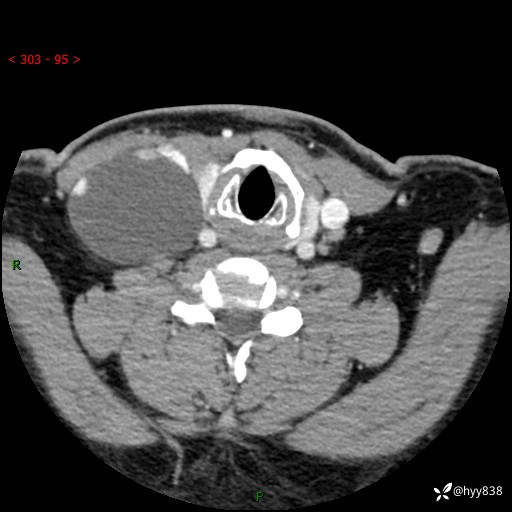

颈部CT平扫+增强